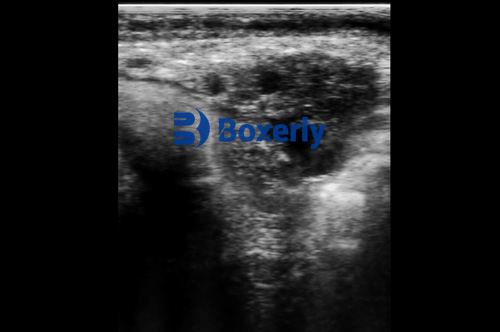

Ultrasonography, particularly B-mode (brightness mode) imaging, provides clear, real-time images of the uterus, fetus, ovaries, and associated structures. It allows the veterinarian or technician to confirm pregnancy as early as 28–35 days post-breeding.

Fetal viability: Can detect heartbeat and fetal motion

Reproductive health: Identifies uterine infections, cysts, and twin pregnancies